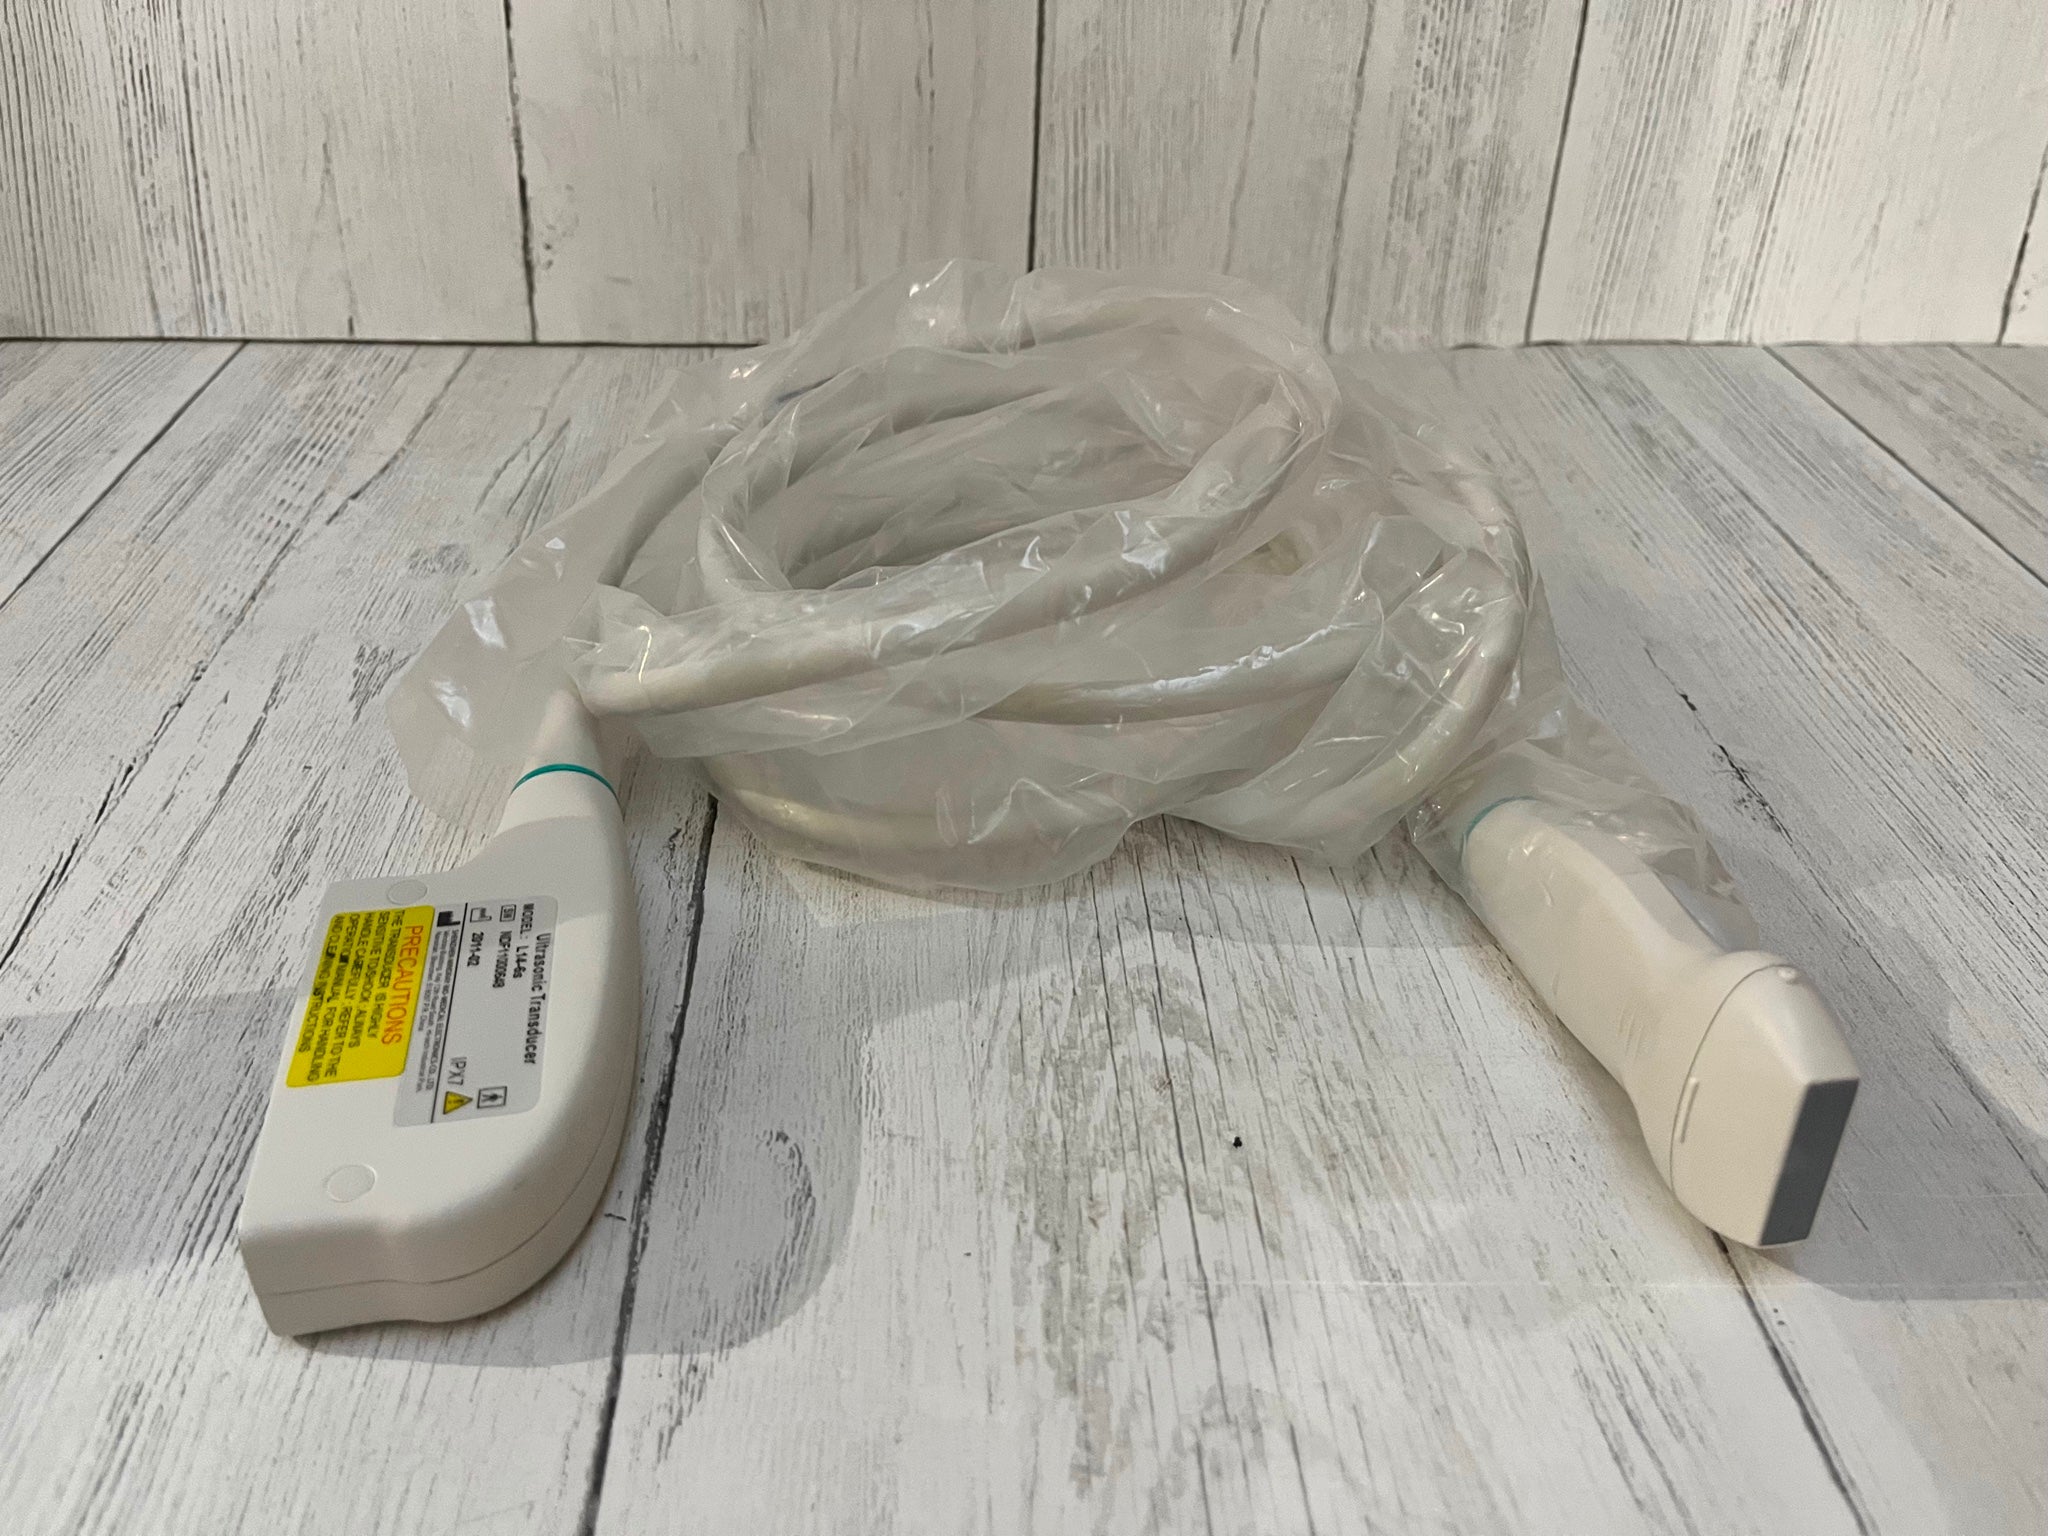

Sonda lineare rettale |

1 |

Sonda convessa |

1 |